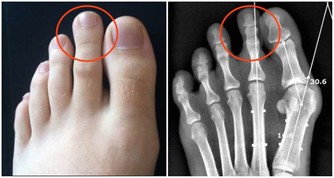

4、骨骼強壯

中醫認為,腎主骨,骨靠腎精滋養,腎好骨才好。腎氣衰敗會出現骨質疏鬆、腰酸背痛,甚至牙齒出現鬆動。